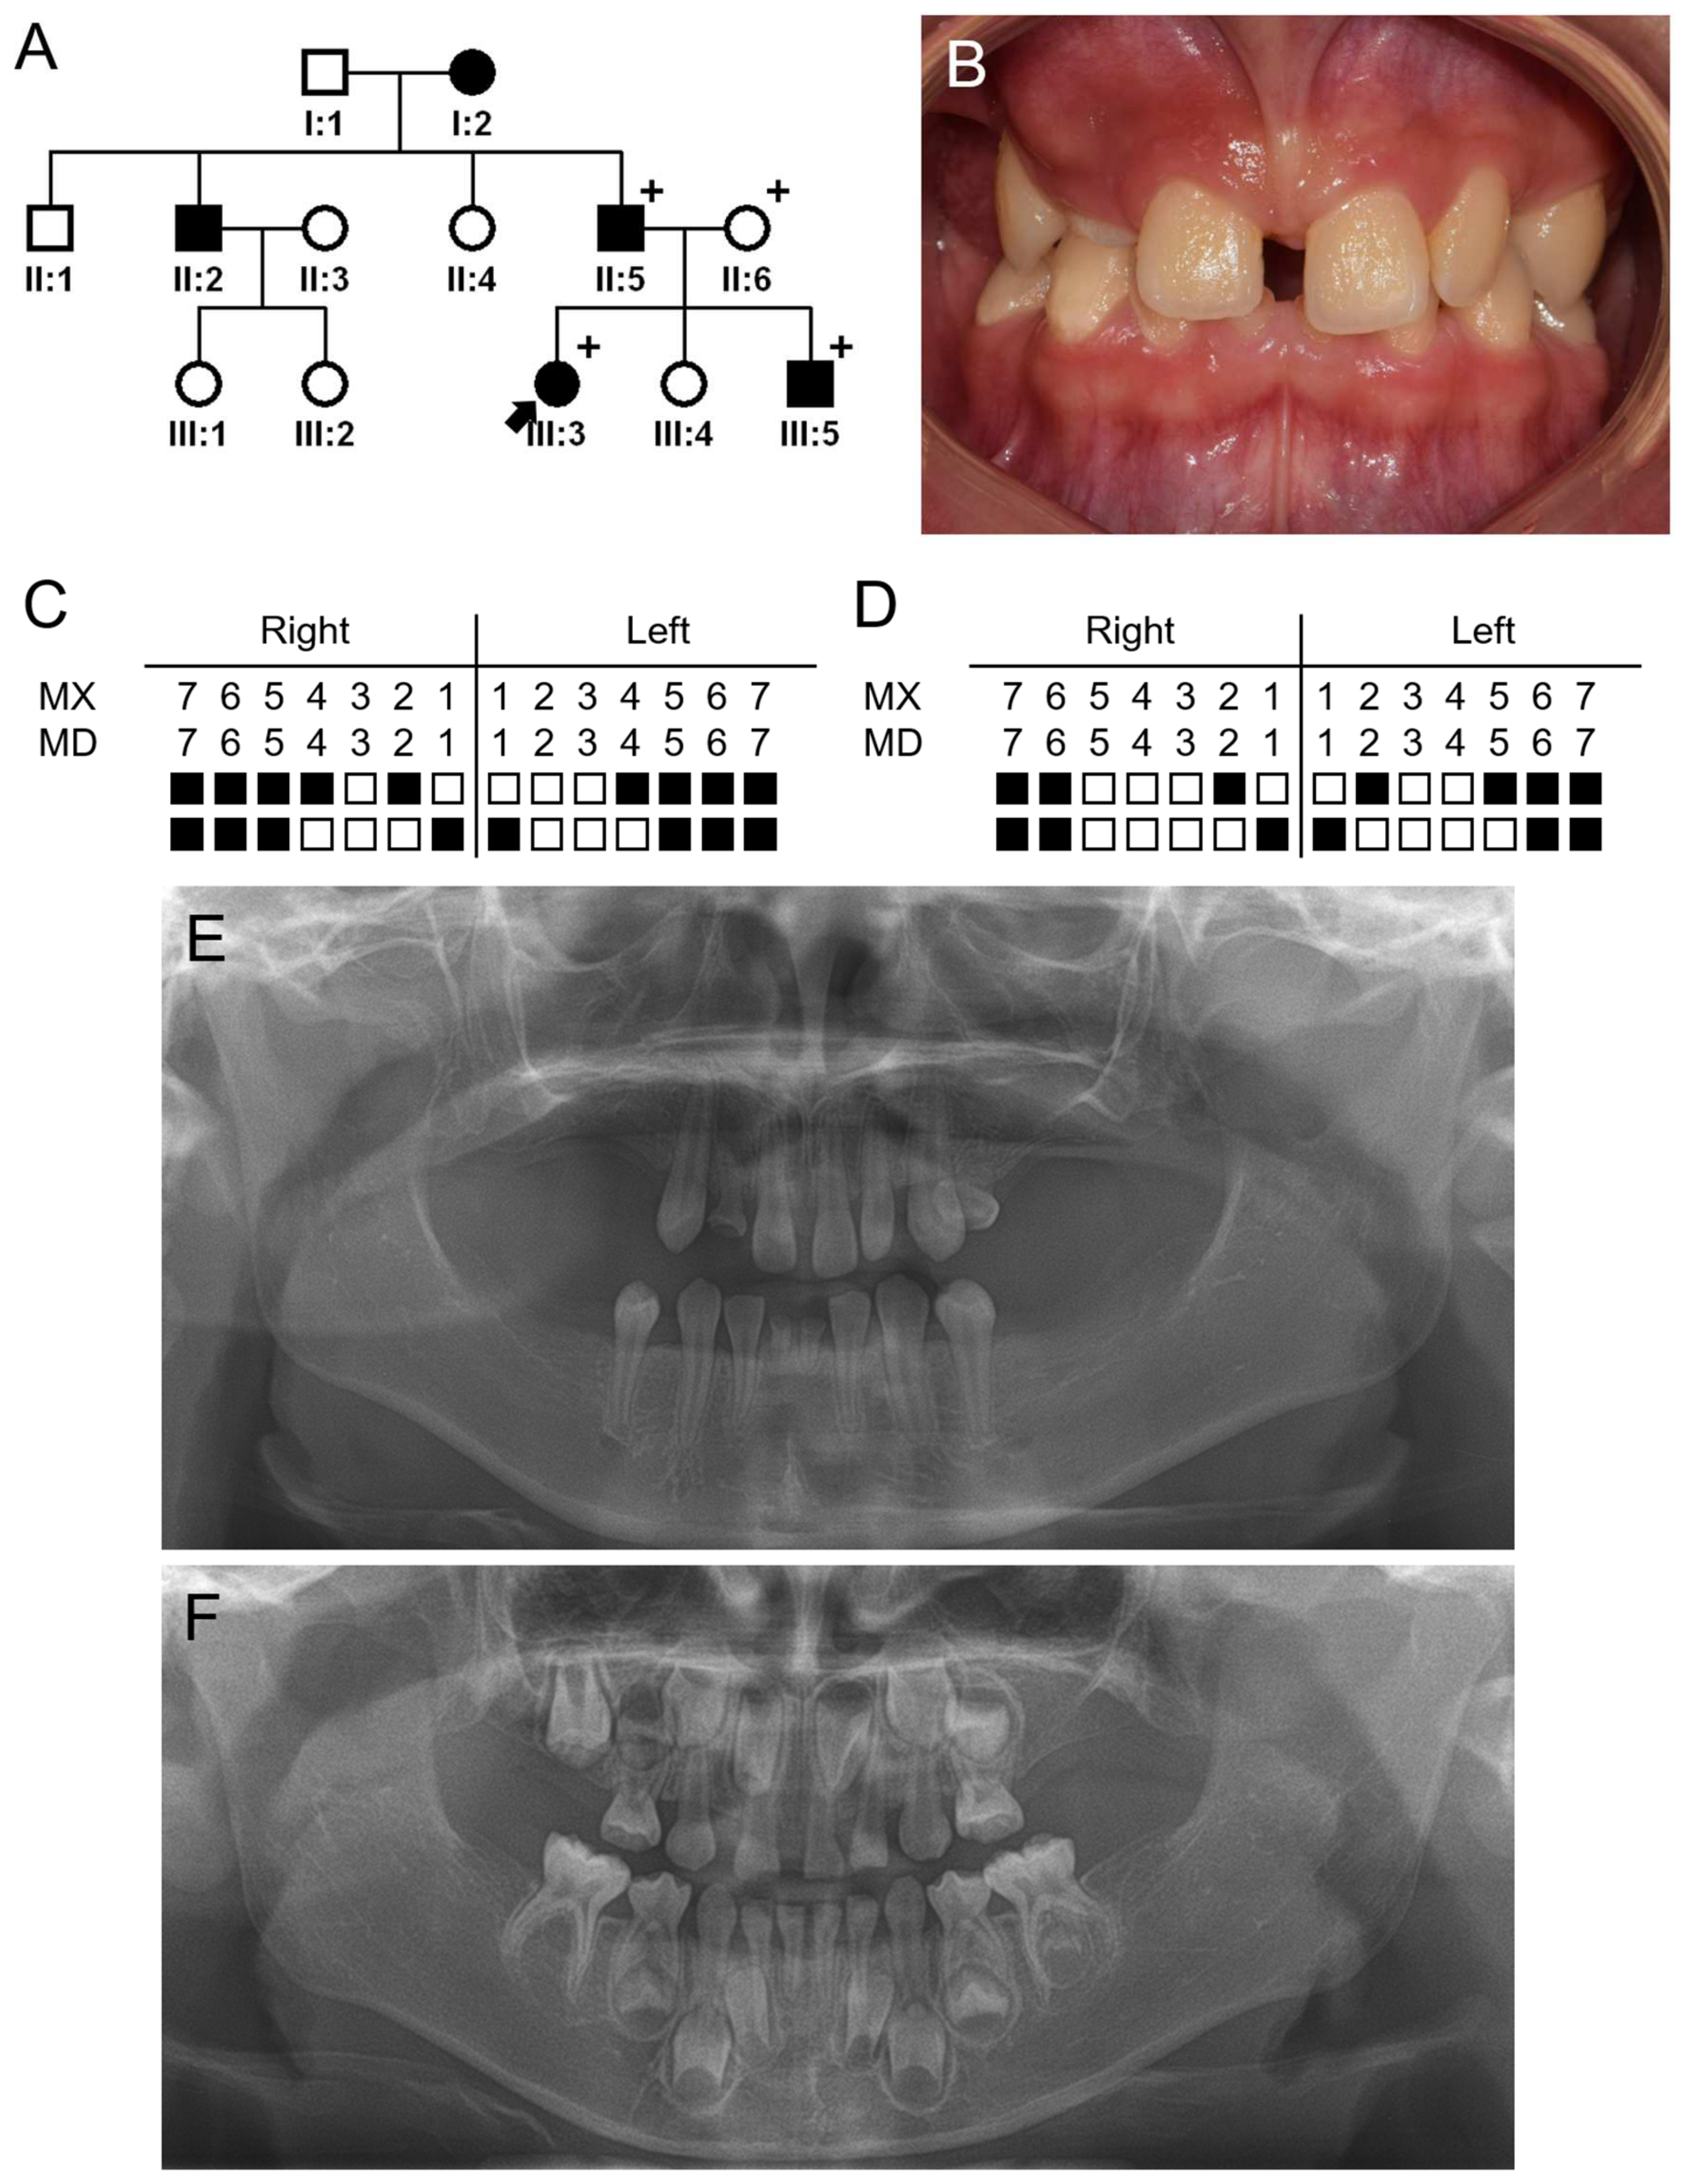

3.1. Family 1